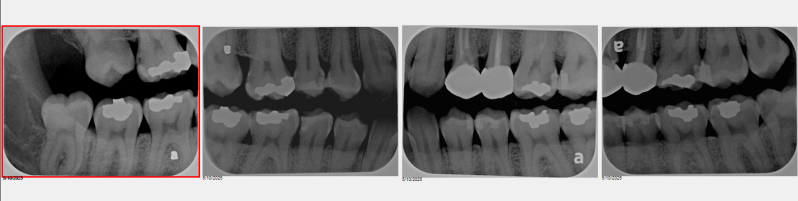

CMS set (with direct sensor)